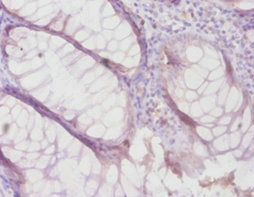

Immunohistochemistry of paraffin-embedded human colon cancer using CSB-PA07419A0Rb at dilution of 1:100